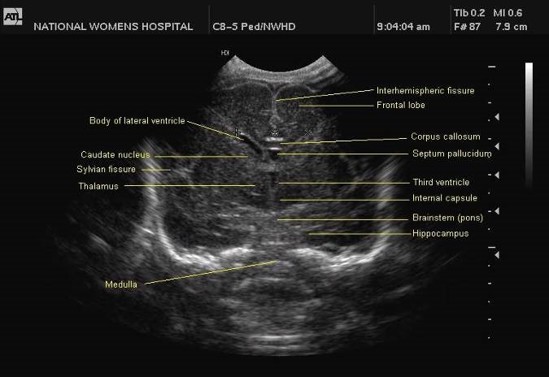

The Ventricular index, as described by Levine, is the absolute distance between the falx and the lateral wall of the anterior horn in the coronal plane at the level of the third ventricle. Values more than 4mm above the 97th centile for gestational age are indicative of significant ventricular dilatation (see chart). A study by Brouwer et al compared early CSF drainage, at a ventricular index of 4 mm above the 97th centile, to drainage beyond this threshold, and showed that early treatment was associated with better development quotient at 2 years and a decreased likelihood of shunt dependence; there was, however, no reduction in the rate of cerebral palsy with early drainage.